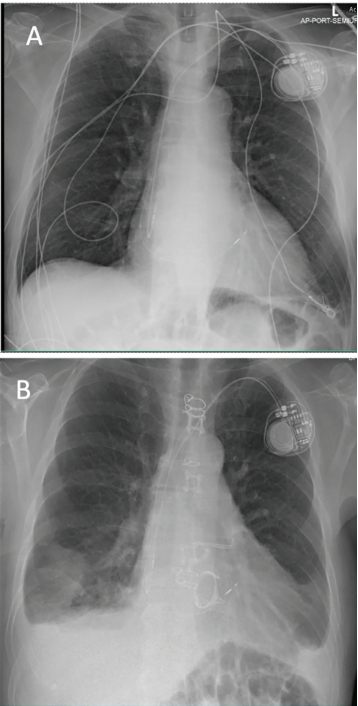

Aortic Valve and posterior chordal-sparing mitral valve replacement using a 31-mm valve (Edwards Lifesciences) without complications. After his surgical recovery, the patient presented to device clinic follow-up for routine pacemaker monitoring. Evaluation showed lack of atrial sensing and no atrial electrograms (Figure 1). A concurrent decrease in atrial unipolar and bipolar lead impedance from 400 ohms to <100 ohms (Figure 2) was also noted. This initial evaluation was consistent with oversensing and possible lead dislodgement. Given these concerns, a chest radiograph was obtained, which confirmed stable lead position without obvious dislodgement (Figure 3). Atrial lead revision was recommended for diagnostic and therapeutic purposes.

Pacemaker impedance describes the structural integrity and electrical performance of leads. Decreases in impedance measurements are consistent with lead insulation breeches, which introduce a second current pathway in parallel to the circuit. Impedance for this patient dropped to below <100 ohms after his surgical intervention, which raised concerns for either lead dislodgement or insulation failure.3 Chest radiography was used to evaluate and showed a stable atrial lead with normal slack. Due to this unremarkable finding, the authors proceeded with lead revision, which showed the entrapment of the lead due to hemostatic clips.